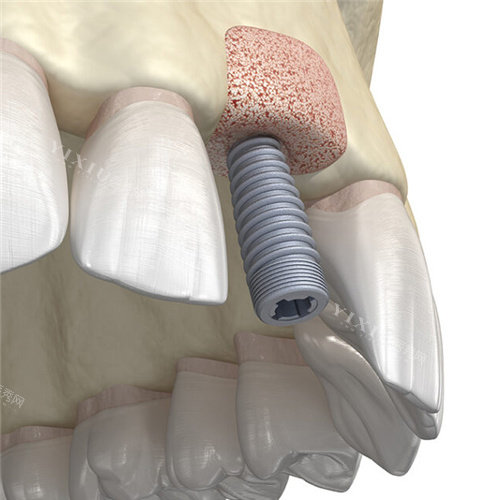

种植牙项目:

即刻种植牙:5980元起

国产创英种植牙:5800元起

韩国登腾种植牙:6200元起

德国BEGO种植牙:8800元起

瑞士ITI种植牙:12800元起

全口种植牙(ALL-ON-4):68000元起